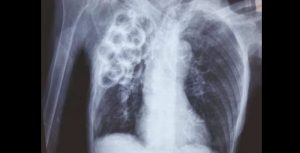

De curieuses opacités pulmonaires en grappe de raisins

Nous rapportons ici de curieuses opacités multiples lobaires supérieures, découvertes fortuitement sur un cliché pulmonaire réalisé dans le cadre du bilan infectieux d’une femme âgée de 85 ans